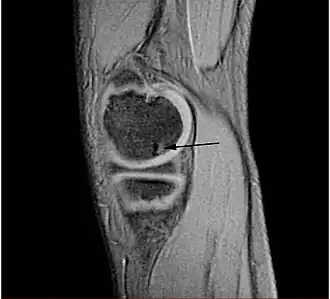

Magnetische kernspinresonantie (MRI) is een bruikbare techniek om de verergering van OCD-beschadigingen in de gaten te houden, om het gewrichtsoppervlak te beoordelen en om normaal botweefsel te kunnen onderscheiden van OCD doordat bot- en kraakbeenoedeem zichtbaar worden op de plek van de ongelijkmatigheden. Een MRI geeft informatie over de toestand van het gewrichtskraakbeen, het bot onder het kraakbeen, oedeem, breuken, vochtophoping, de toestand van het gewrichtsoppervlak en de verplaatsing van losse fragmenten. Bij actieve beschadigingen is er een lage signaalintensiteit op een T1-gewogen opname en een hoge signaalintensiteit op een T2-gewogen opname. Dit duidt op een onstabiele beschadiging of recente microbreuken. MRI en artroscopie geven samenhangende resultaten. Uit röntgenopnames zijn minder snel conclusies te trekken dan uit MRI-resultaten.